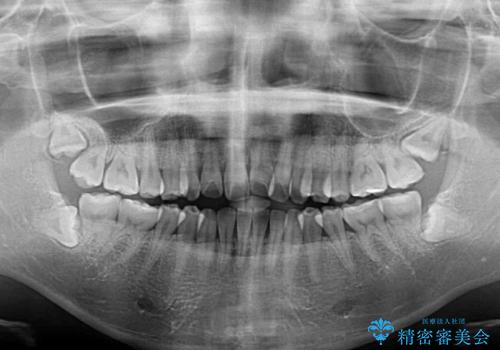

- 飛び出した前歯と口元の突出感を気にして来院された患者様です。

奥歯の咬み合わせを見ると、上顎が下顎に対して相対的に前方にありました。

口元の突出感を改善するためには、上顎臼歯を後方に移動させた咬み合わせにする必要があります。